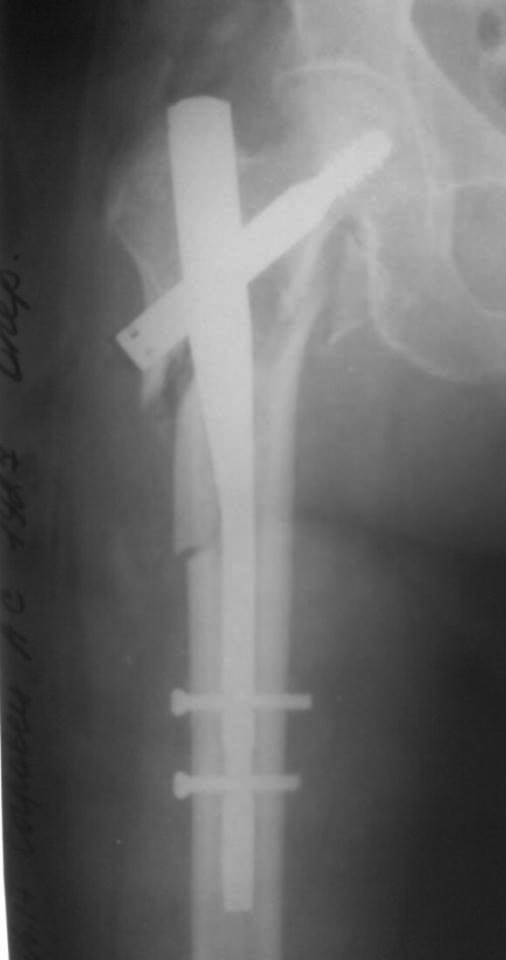

Это длинная псевдограмма, как понимаете, Ее сложно сзади завести, с ЭОПа только эта картинка, я за соседним столиком оперировал, парни пытались погнуть - обломился, в итоге поставили короткую, репозиция примерно такая же, снимки могу завтра -послезавтра выложить. У нас уже были проблемы с этим стержнем в плане переднего Кортекса, да и другие тоже, у них на проксимальный винте не "борозды" , а "царапины" - либо блокировать наглухо либо ротационной стабильности нет, да и прямая как шпага((((

Как-то так

заднего захода тут точно нет,а чуть кпереди - здесь бы ничего не решило (делали и так). Это уже не первый раз такое с этими гвоздями. Просто уже накипело. Чуть поуже или покривее бедро - упираются в передний кортекс. У многих что-то вроде tip pain. Было 2 периимплантных перелома, на мой взгляд связанных именно с этим. Сломался по дырке, мне кажется и в тисках не получится, сплав какой-то непластичный совсем.